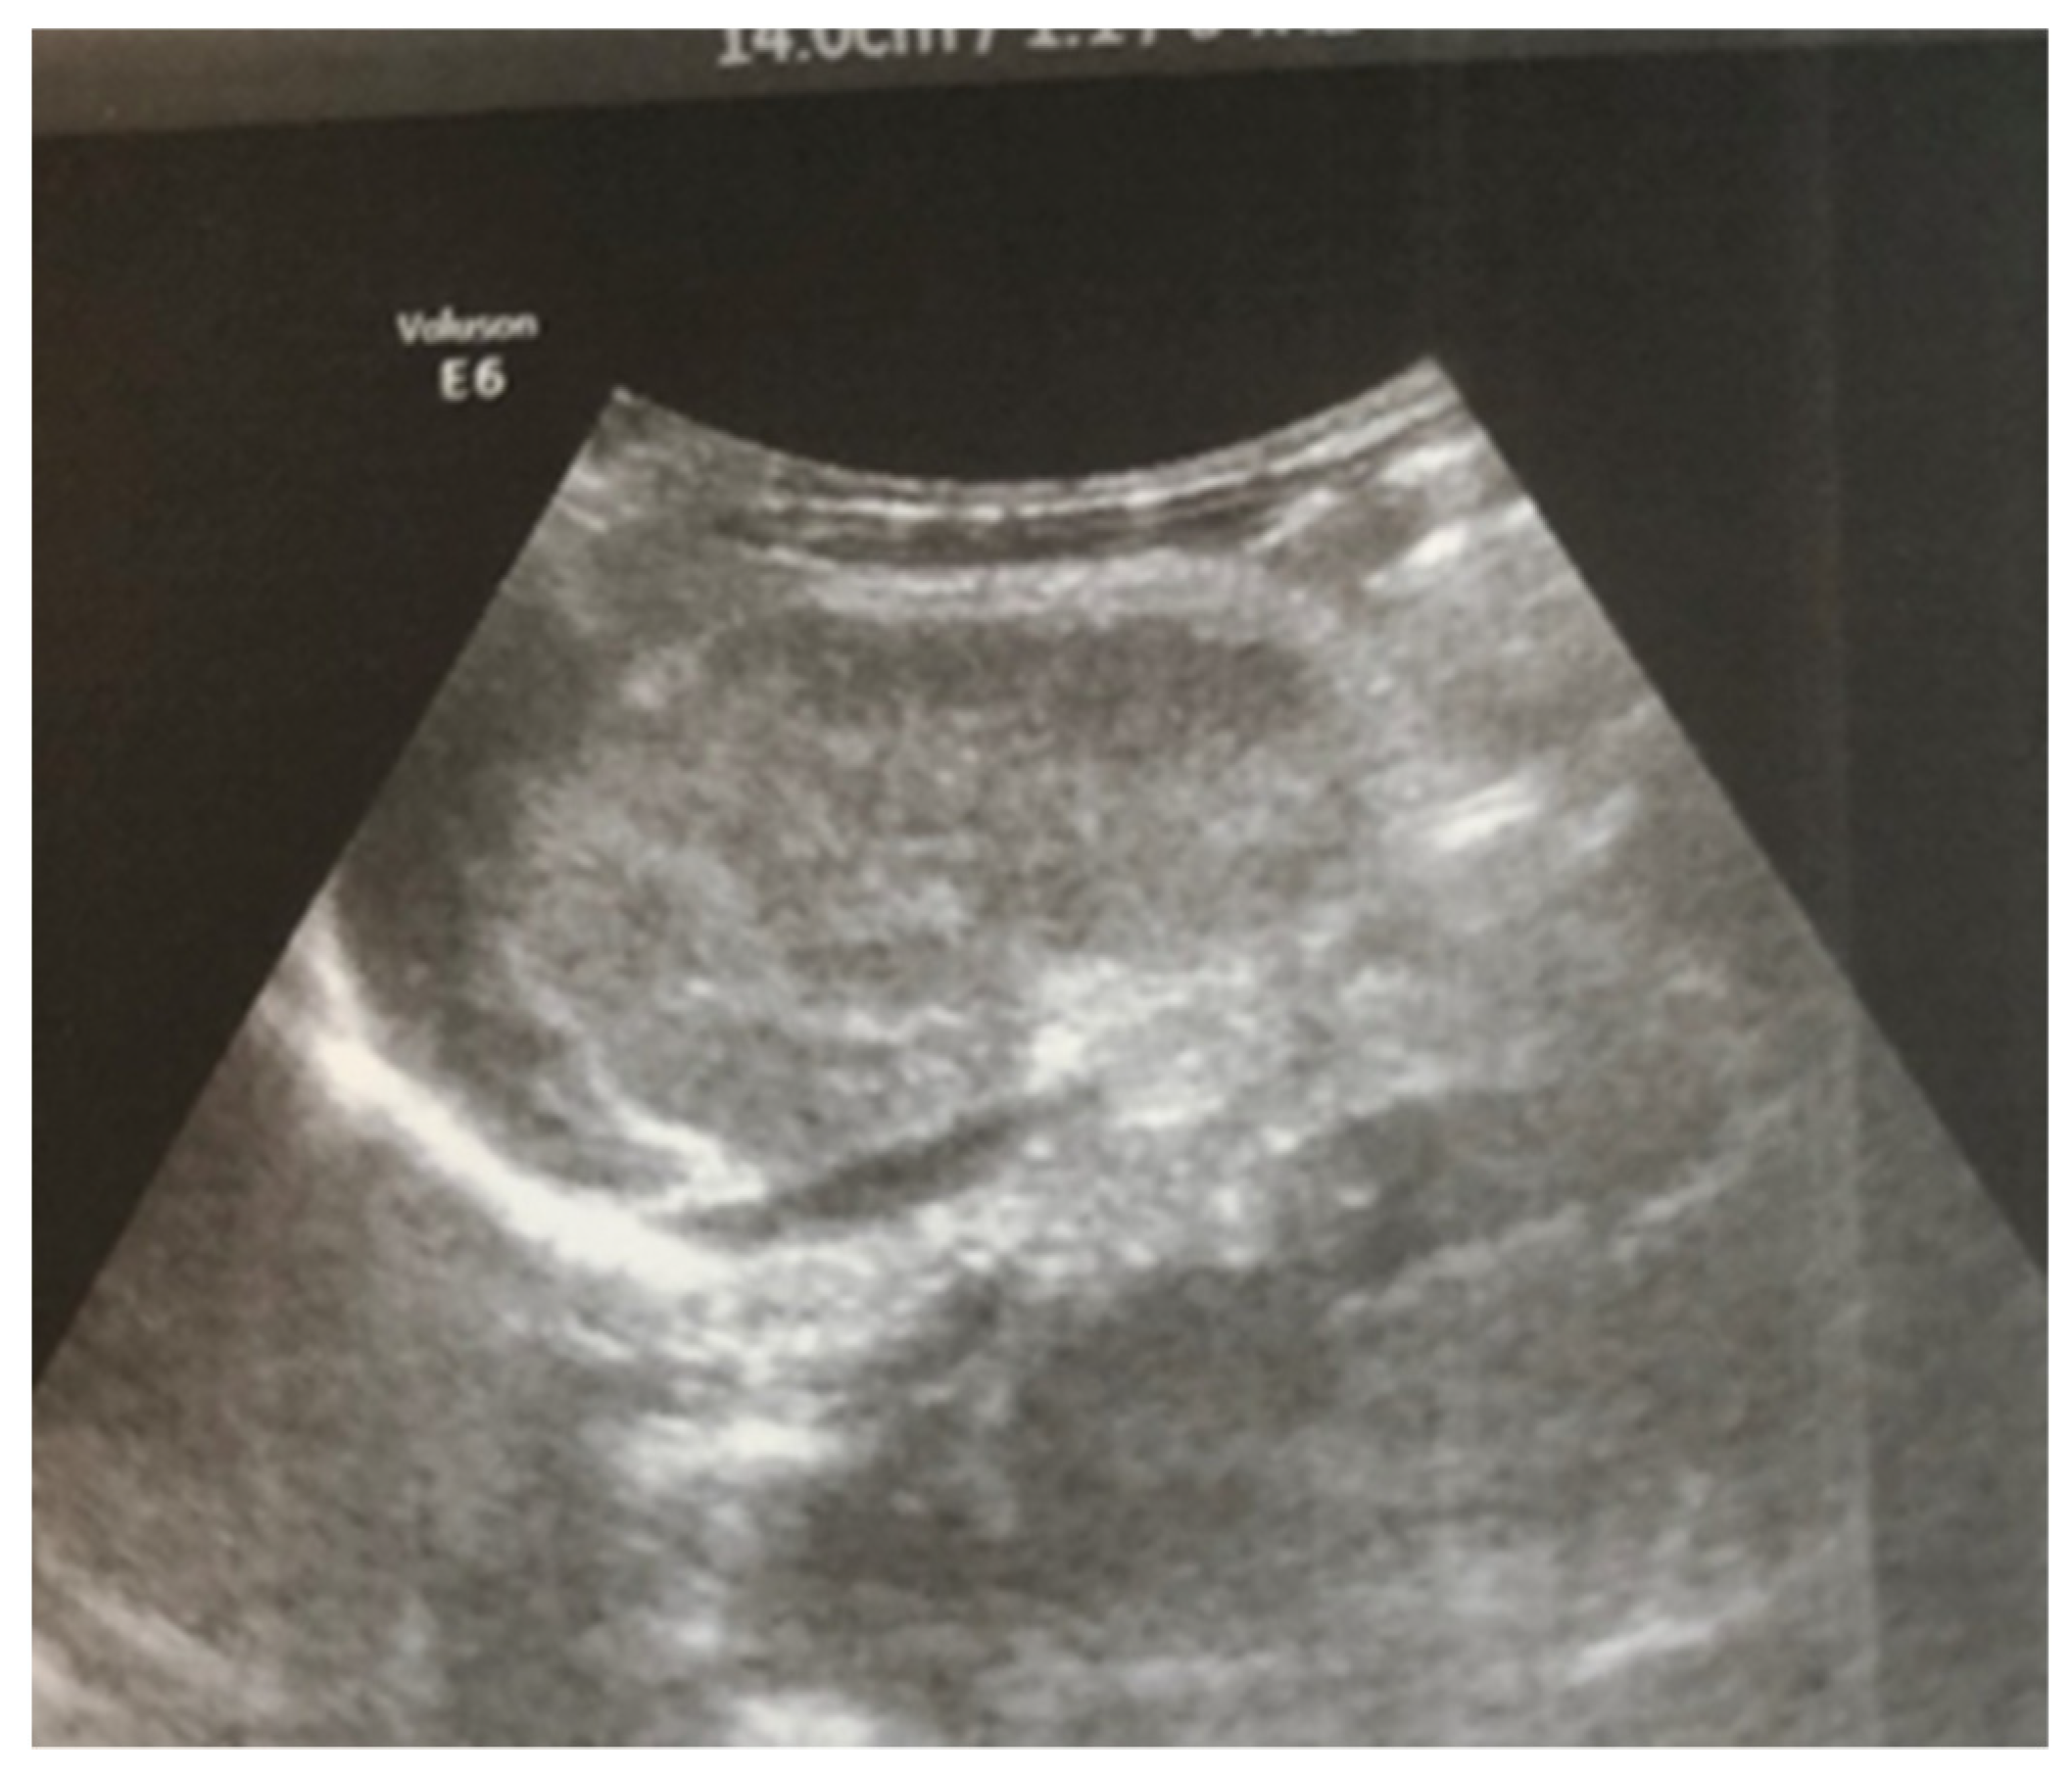

Complex therapy was performed—mechanical ventilation, antibiotics in doses adjusted according to creatinine clearance, anticonvulsants, low-molecular-weight herapin (Enoxaparin), inotropic (Dopamine), and phototherapy. The child’s condition gradually improved and he was extubated on the 9th day of the stay in the NICU. An uncomplicated post-extubation period followed. In the following 2–3 days, macroscopic hematuria was observed. On the second day after extubation, the child’s diuresis was good. The condition of the right kidney was monitored by ultrasound on the 3rd day (Figure 3), the 10th day (recovery of renal venous blood flow was observed), and at the end of the first month. On the 10th day, a decrease in kidney size was noted, and at the end of the first month, the size was below the norm for the age—i.e., the onset of renal atrophy. Follow-up examinations at 6 months and 1 year showed evidence of the atrophying of the right kidney with a longitudinal size of 2 cm, the occurrence of compensatory hypertrophy of the left kidney, normal blood pressure, and preserved renal function (Figure 4).

Figure 3. Right kidney image taken on the third day after birth—increased size, increased echogenicity of the parenchyma, and loss of cortico-medullary differentiation.

Ultrasound examination is the main tool for the detection and follow-up of renal vein thrombosis [10]. Neonatal venous thrombosis usually arises gradually from the small venous branches and spreads to the main renal vein. In the first stage of thrombosis, interlobular and interlobar hyperechoic stripes are observed, the kidney is enlarged in size, and it becomes spherical with hypoechoic pyramids [7]. These hyperechoic stripes are in fact the thrombosis of the small interlobular and/or interlobar veins with perivascular hemorrhage and edema [11]. In the later stage, after the first few days, the kidney becomes heterogeneous, with a loss of cortico-medullary differentiation. Doppler ultrasound examination may show reduced amplitude or a missing venous signal. After about two weeks, a decrease in the size of the injured kidney occurs, along with hypoechogenicity in the area of the medulla, caused by the liquefaction (liquefaction) of the kidney tissue. Over time, in a large percentage of cases, atrophy develops with the renal function decrease and contralateral hypertrophy of the other kidney [5,7]. In most cases, ultrasound is sufficient for diagnosis, but in unclear cases, a CT scan of the kidneys may be performed. In the presented case, the diagnosis and disease progression were also monitored through ultrasound surveillance, performed daily during the first days after birth. This allowed for the tracking of the characteristic changes in renal venous thrombosis in the neonatal period. Due to the critical condition of the infant, contrast angiography was not performed.